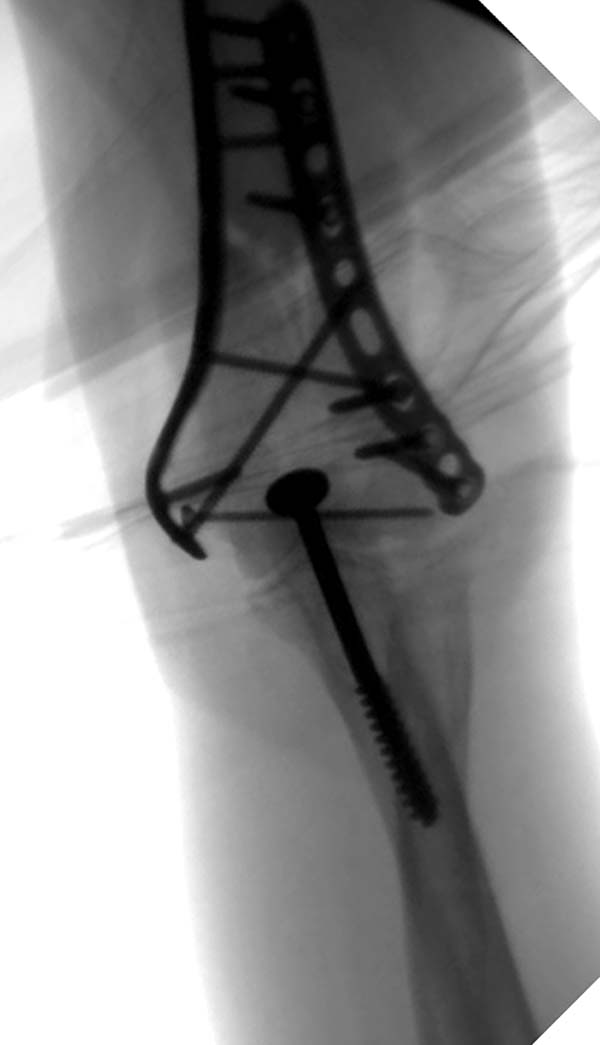

Примеры: первому более 15 лет фиксирован шурупом и tension band

technique, а второй перелом открытый больной 80 лет, после наружного

фиксатора в первом этапе и окончательная фиксация вторично. Третьий раз

внесуставная остеотомия...

-----------   -----------

Вложение не в текстовом формате было извлечено&hellip;

Имя     : 2-5 Distal Humerus CRM.JPG

Тип     : image/jpeg

Размер  : 30977 байтов

Описание: отсутствует

Url     : http://weborto.net:8080/pipermail/ortho/attachments/20130604/c45a379f/attachment-0007.jpeg